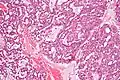

| Low magnification micrograph of a polymorphous low-grade adenocarcinoma, showing the typical variation of architectural arrangement. H&E stain. | |

Polymorphous low-grade adenocarcinoma (PLGA) is a rare, asymptomatic, slow-growing malignant salivary gland tumor.[1] It is most commonly found in the palate.[2]

- It has a varied microscopic architectural appearance, i.e. it is polymorphous.

- It is non-aggressive when compared to other oral cavity tumors, i.e. it is a low-grade tumor.[1]

- It forms glands, i.e. it is an adenocarcinoma.

PLGAs consist of a monomorphous cell population that has a varied histologic morphology.

Microscopically, its histology can be confused with an adenoid cystic carcinoma and a pleomorphic adenoma.